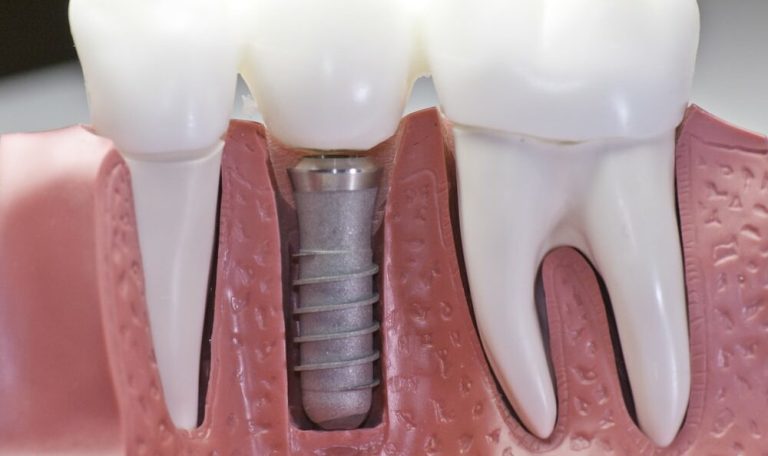

İmplant tedavisi iyileşme süresi ve tedavi aşamaları, diş eksikliği yaşayan birçok kişinin aklındaki en önemli konular arasında yer alır. Modern diş hekimliğinin sunduğu en etkili çözümlerden biri olan implant tedavisi, estetik ve fonksiyonel açıdan uzun vadeli sonuçlar sunar. Ancak..